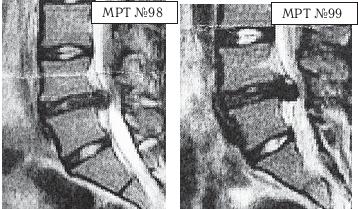

МРТ № 4

МРТ № 5

На МРТ № 4 наблюдается межпозвонковый диск в начальной стадии развития дегенеративно-дистрофического процесса.

На МРТ № 5 наблюдается межпозвонковый диск на более поздней стадии развития дегенеративно-дистрофического процесса.